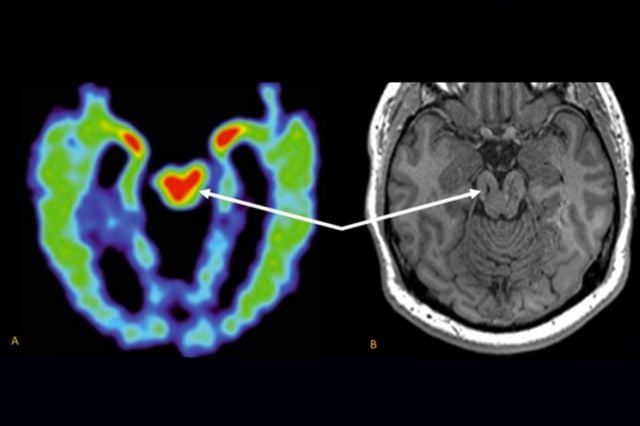

Doctors must conduct an autopsy to look for signs of brain tissue degeneration and a buildup of abnormal tau proteins. CT enterography CTE is a technique that provides detailed images of the small bowel by using a low Hounsfield unit oral contrast media. The scans were color-coded.

This is a brain disease for which there is no treatment. The results which were published in the Journal of Alzheimers Disease recently may provide new insights into CTE which is currently only diagnosable in post-mortem analyses. The study indicated an experimental positron emission tomography PET scan can detect an indication of CTE.